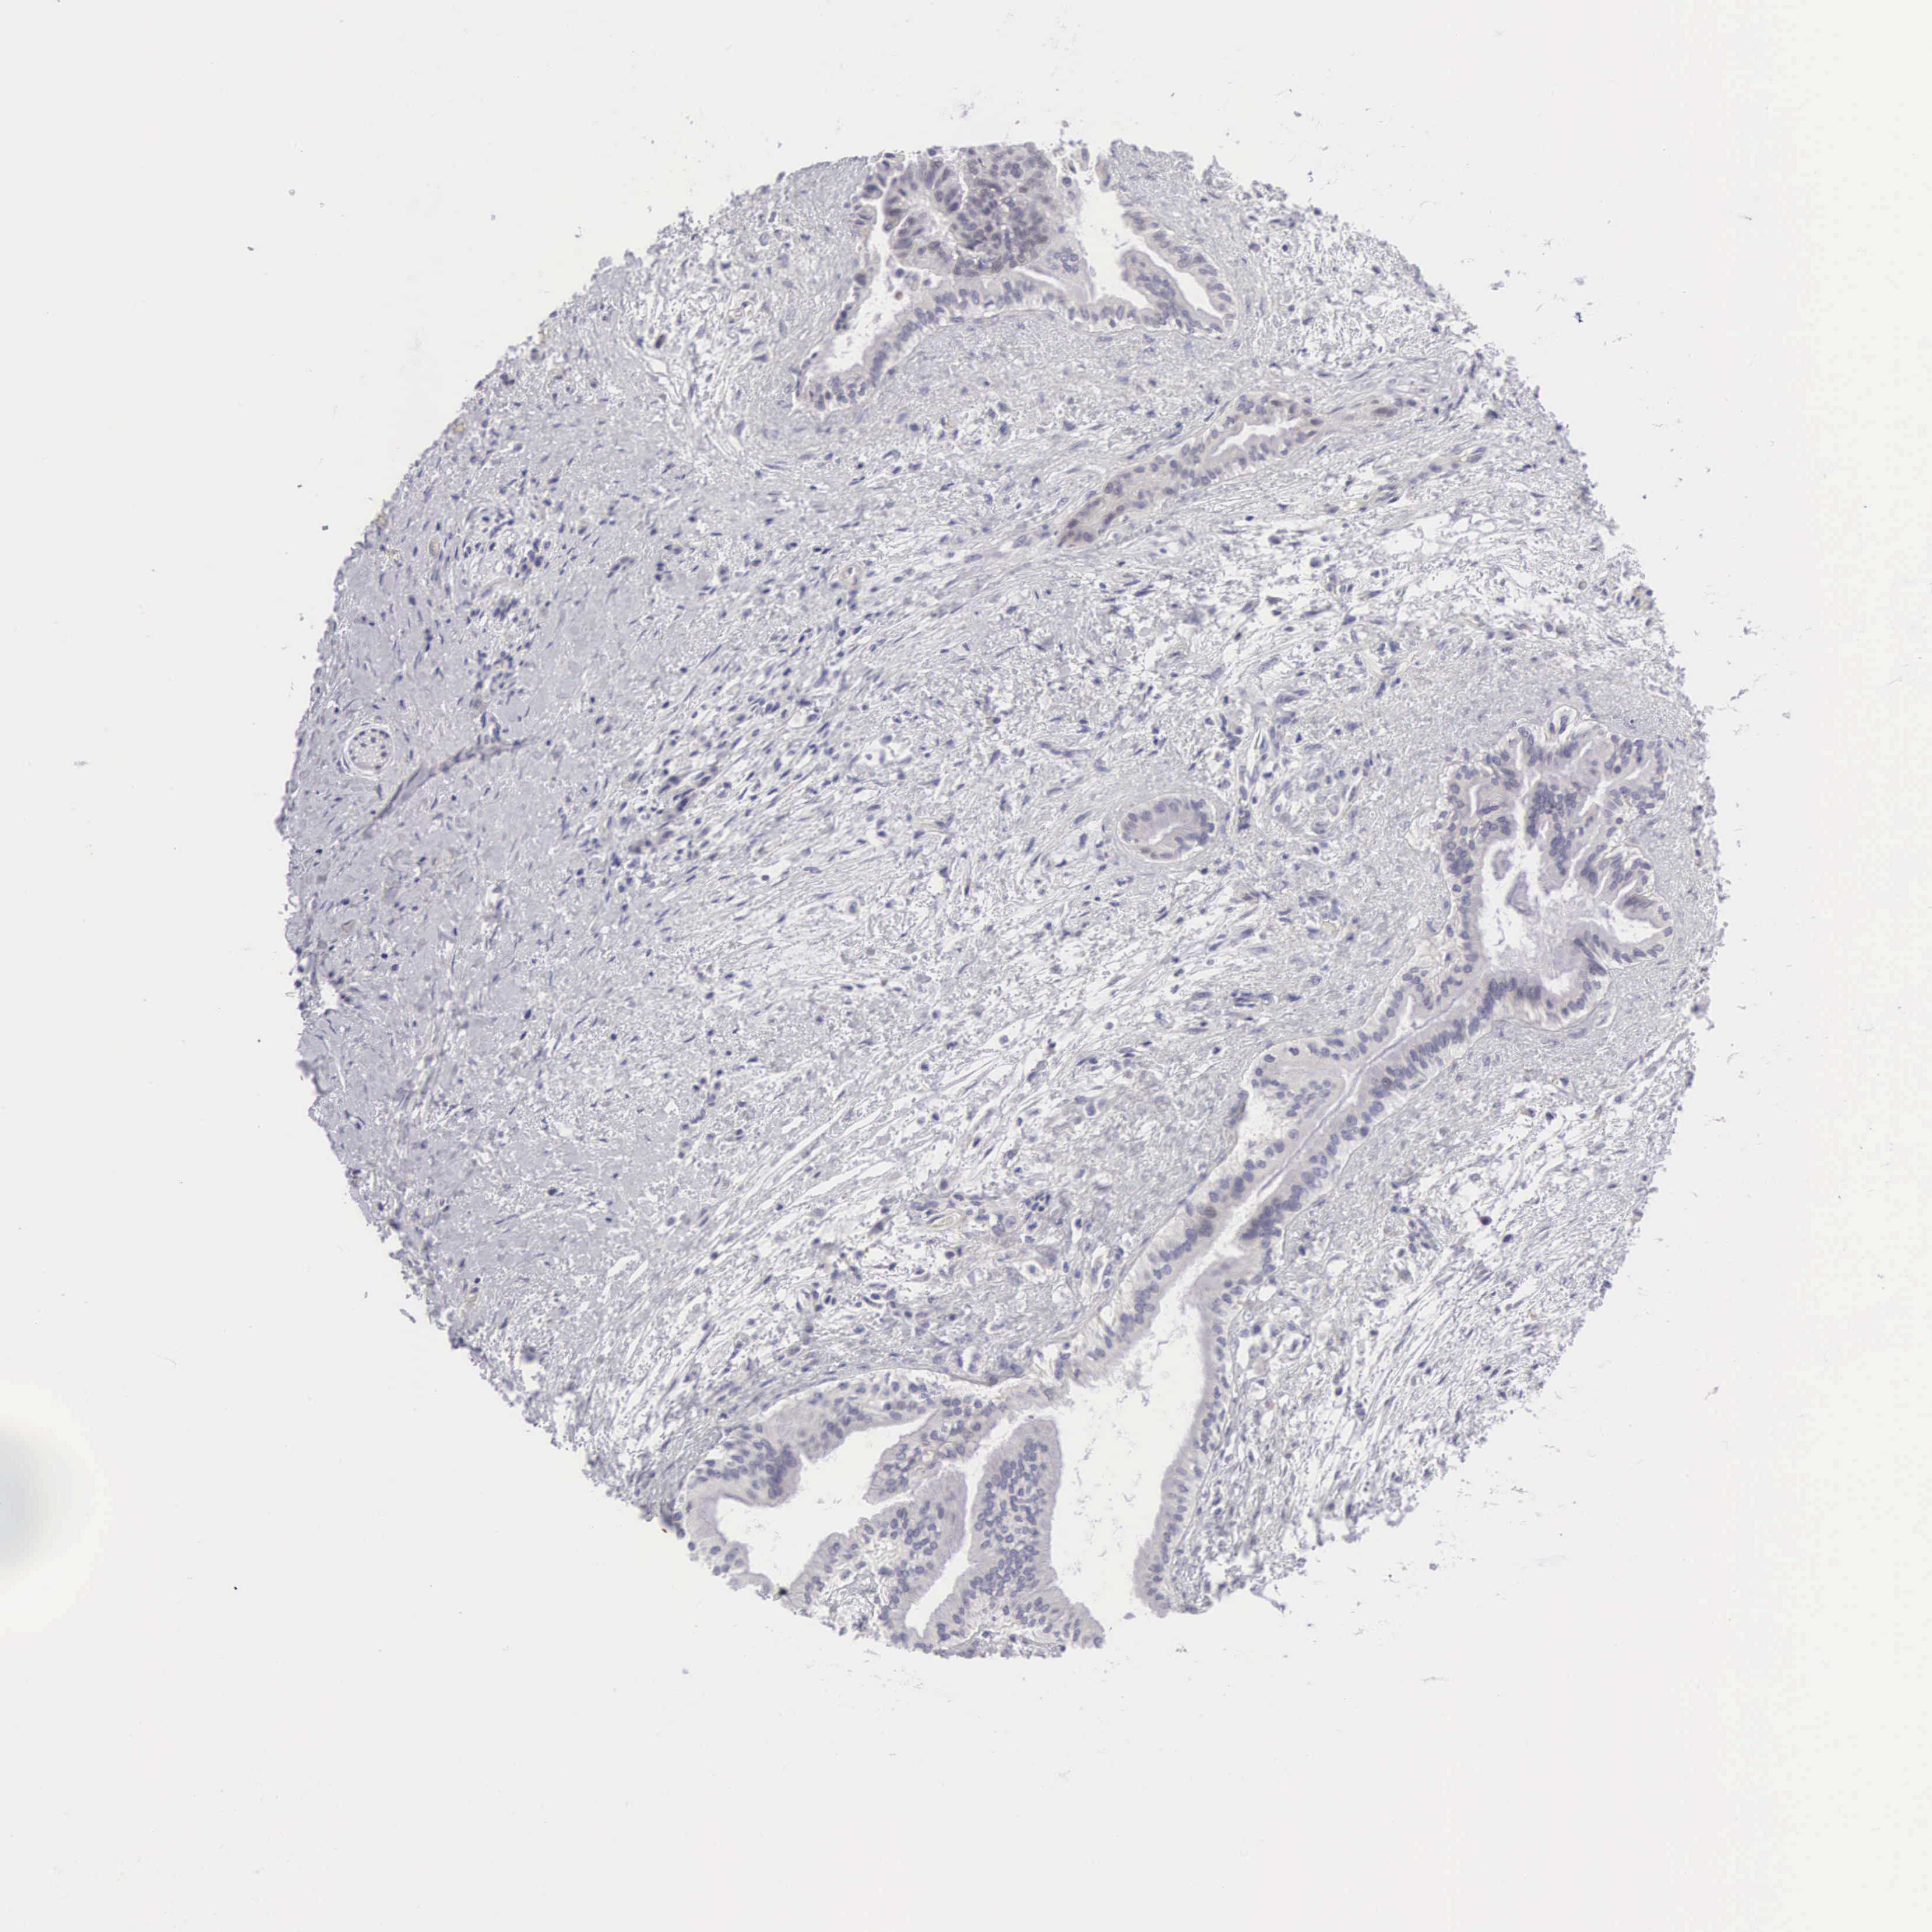

PANCREATIC CANCER - Protein expressioni

A mouse-over function shows sample information and annotation data. Click on an image to view it in a full screen mode. Samples can be filtered based on level of antibody staining by selecting one or several of the following categories: high, medium, low and not detected. The assay and annotation is described here.

Note that samples used for immunohistochemistry by the Human Protein Atlas do not correspond to samples in the TCGA dataset.

Antibody stainingi

Antibody staining in the annotated cell types in the current human tissue is reported as not detected, low, medium, or high, based on conventional immunohistochemistry profiling in selected tissues. This score is based on the combination of the staining intensity and fraction of stained cells.

Each image is clickable and will lead to virtual microscopy that enables deeper exploration of all samples and also displays staining intensity scores, fraction scores and subcellular localization as well as patient and tissue information for each sample.

Antibody HPA000536

Antibody CAB056152

Antibody CAB056153

Adenocarcinoma, NOS